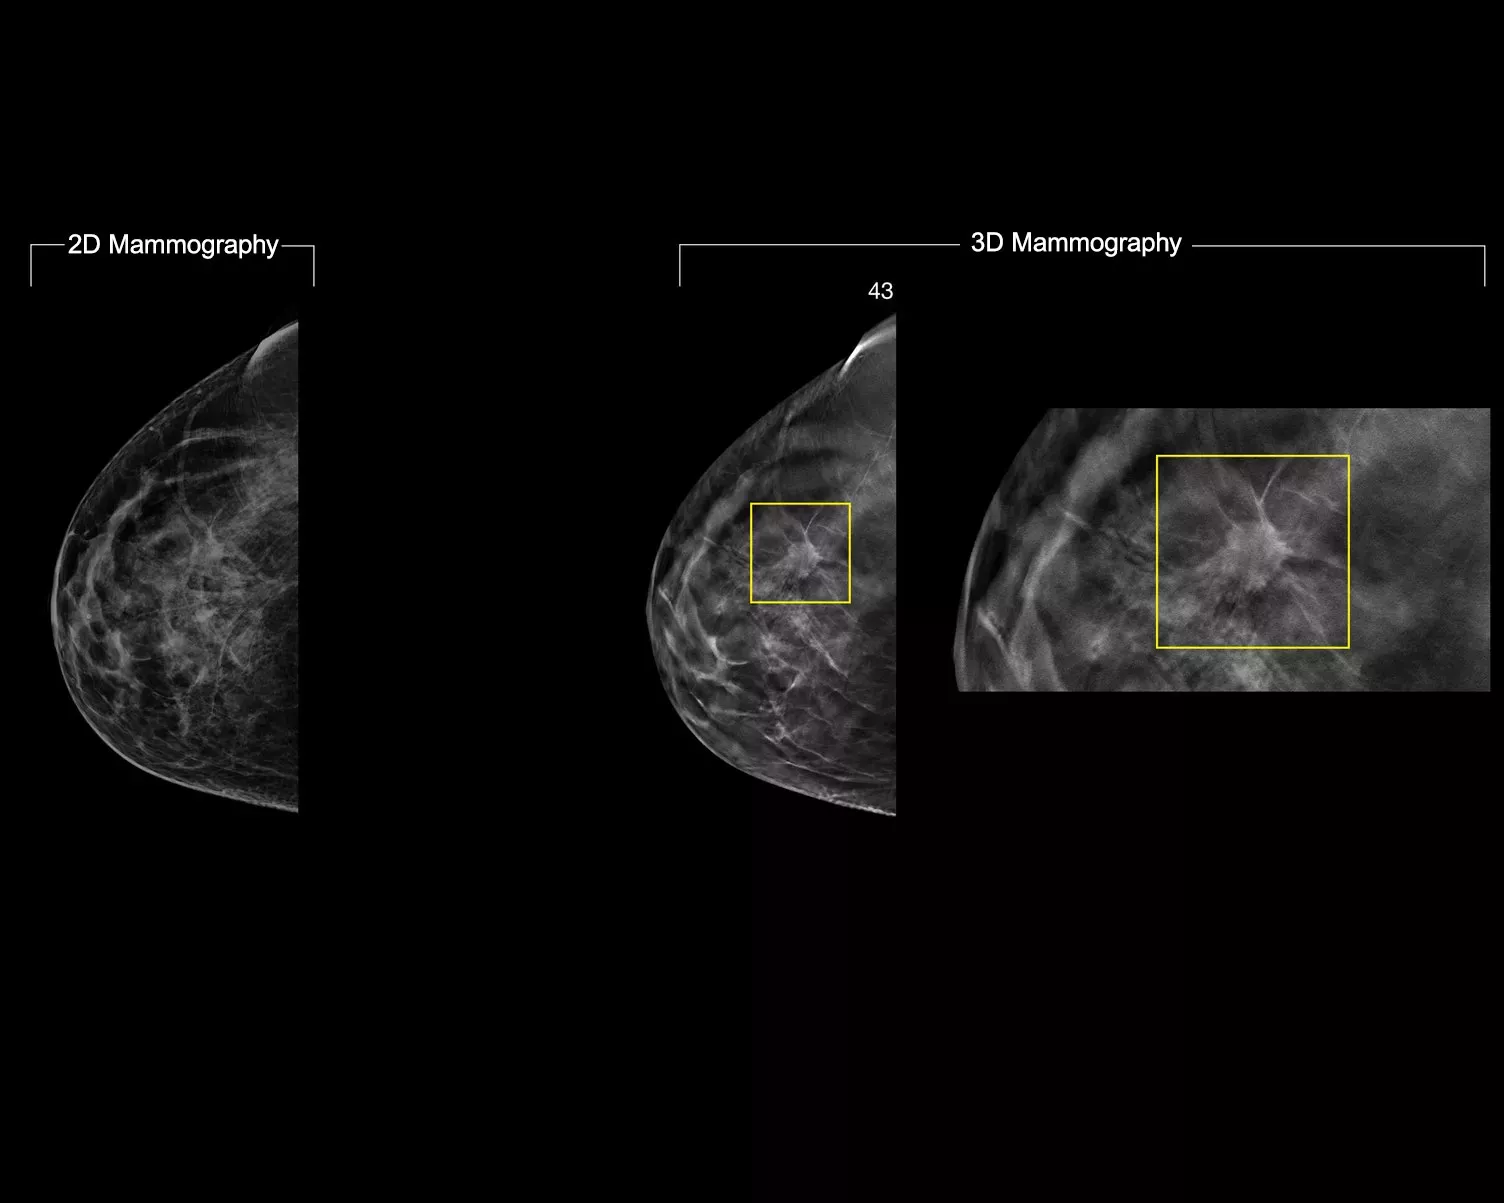

Die intelligent 2D-Bildgebungstechnologie erzeugt mittels KI-Unterstützung robuste und dennoch natürlich aussehende, synthetische 2D-Bilder in Korrelation mit den 3D-Mammografiedaten. Dies ermöglicht Radiologen eine schnelle und zuverlässige Erkennung kleinster mammografischer Charakteristika und der Läsionsmorphologie.*

Mehr klinisch relevante Details aus hochauflösenden 3D-Mammografiedaten. Nutzen Sie KI-gestützte Analysen zur sicheren Visualisierung von feinen Gewebemerkmalen und Läsionen in den rekonstruierten, synthetischen 2D-Aufnahmen.

• Ermöglicht den sofortigen Übergang von den verdächtigen Bereichen auf dem 2D-Bild zum POI auf dem 3D-Mammografie-Schnittbild.